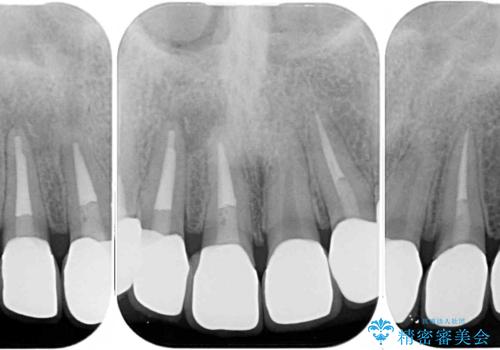

必要に応じて根管治療を行い、前歯6歯をオールセラミッククラウンで補綴することとしました。

治療途中に出産を迎えるため、下顎前歯のデコボコを部分矯正で改善し、上下前歯を綺麗に仕上げることとしました。